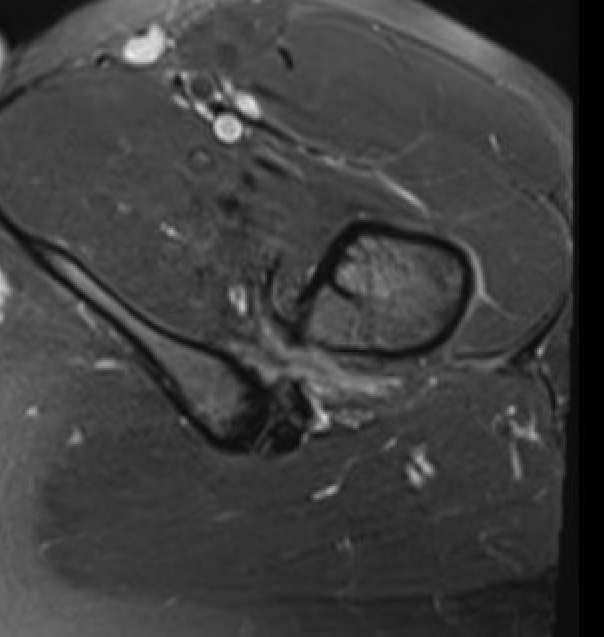

MRI

Reduced ischiofemoral space - distance between the lesser trochanter and the ischial tuberosity

Reduced quadratus femoris space - distance between hamstring tendon and iliopsoas

Inflammation / edema in quadratus femoris +/- fatty degeneration